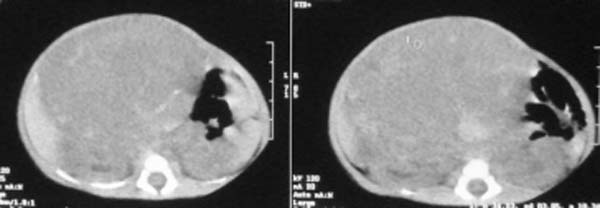

这个女孩刚出生一天,肚子比较大,没任何症状.比较少见,请大家积极发言!!

这个病例定位诊断:1、可以肯定肿块不在肝脏。2、肿块在腹膜后,因为肠管向前侧方推移,肾脏明显向后推挤,腹主动脉及下腔静脉被肿块包绕。

定性诊断比较困难,该病例肿块为实质性,小儿最常见的腹膜后肿瘤第一位应该是-----神经母细胞瘤!

我的意见是-----定位诊断是“1、可以肯定肿块不在肝脏。2、肿块在腹膜后,因为肠管向前侧方推移,肾脏明显向后推挤,腹主动脉及下腔静脉被肿块包绕。”